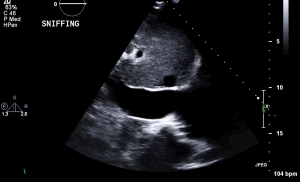

1 RVF PLAX

17 RVF Subcostal IVC Sniff